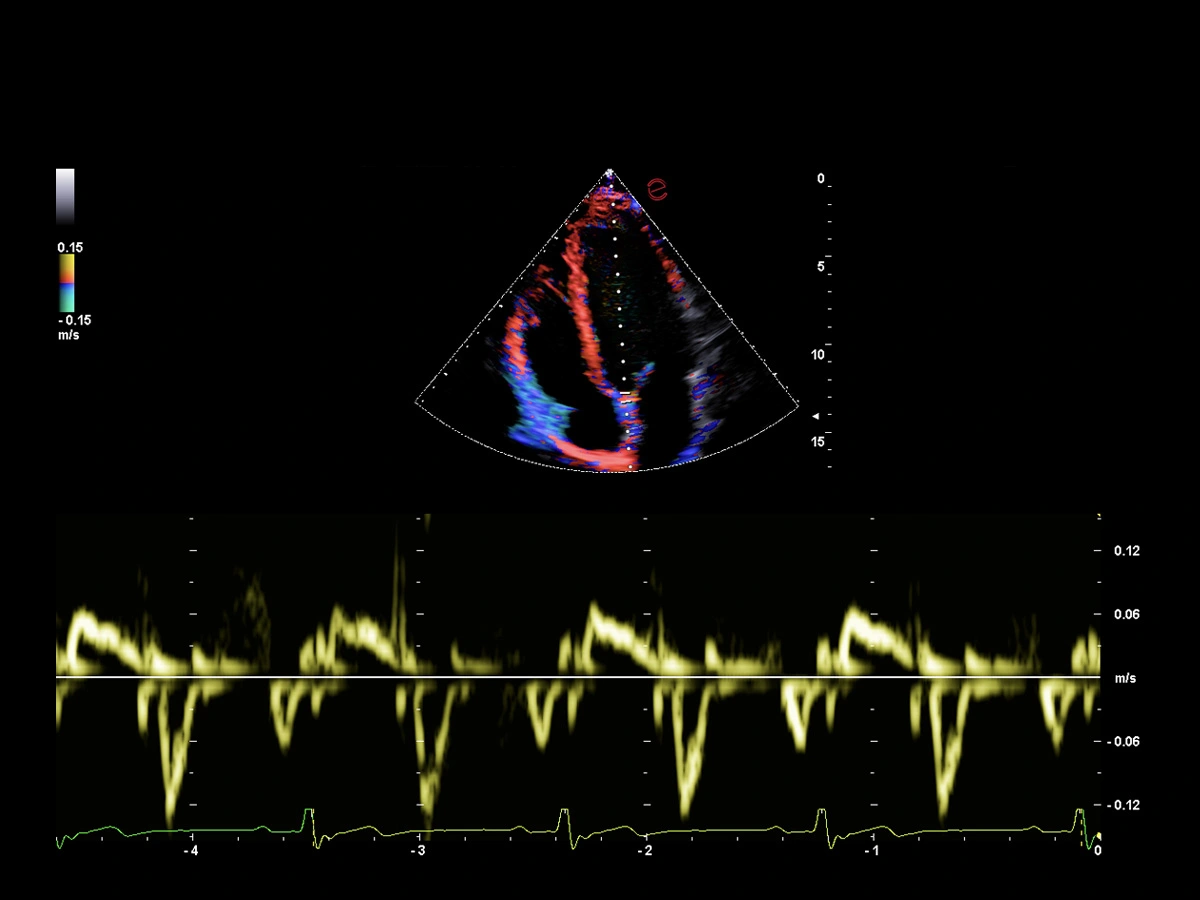

Innovative hemodynamic assessment with HyperDoppler

Esaote’s HyperDoppler technology provides an advanced visualization of intracardiac blood flow dynamics, offering clinicians an intuitive understanding of complex hemodynamics that goes beyond conventional Doppler imaging. By generating real-time vector maps, streamlines, and vortex formations, HyperDoppler enables the detailed assessment of diastolic function, ventricular dyssynchrony, and valvular abnormalities.

This unique flow visualization supports earlier detection of subtle dysfunction, particularly in challenging cases such as heart failure, prosthetic valve evaluation, and structural heart disease. HyperDoppler’s zero-click, visually rich interface enables faster, more comprehensive exams, allowing cardiologists to make more informed clinical decisions.